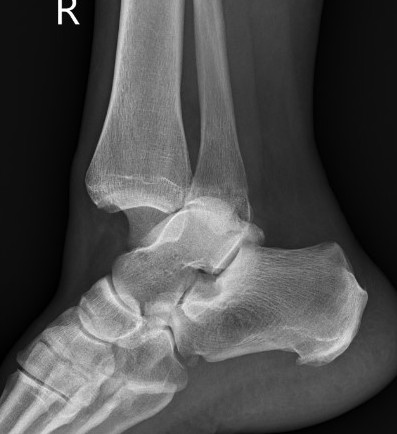

Xray

Ankle fractures with deltoid ligament rupture / Bimalleolar equivalent injury

Maisonneuve injury with proximal fibular fracture and increased medial clear space